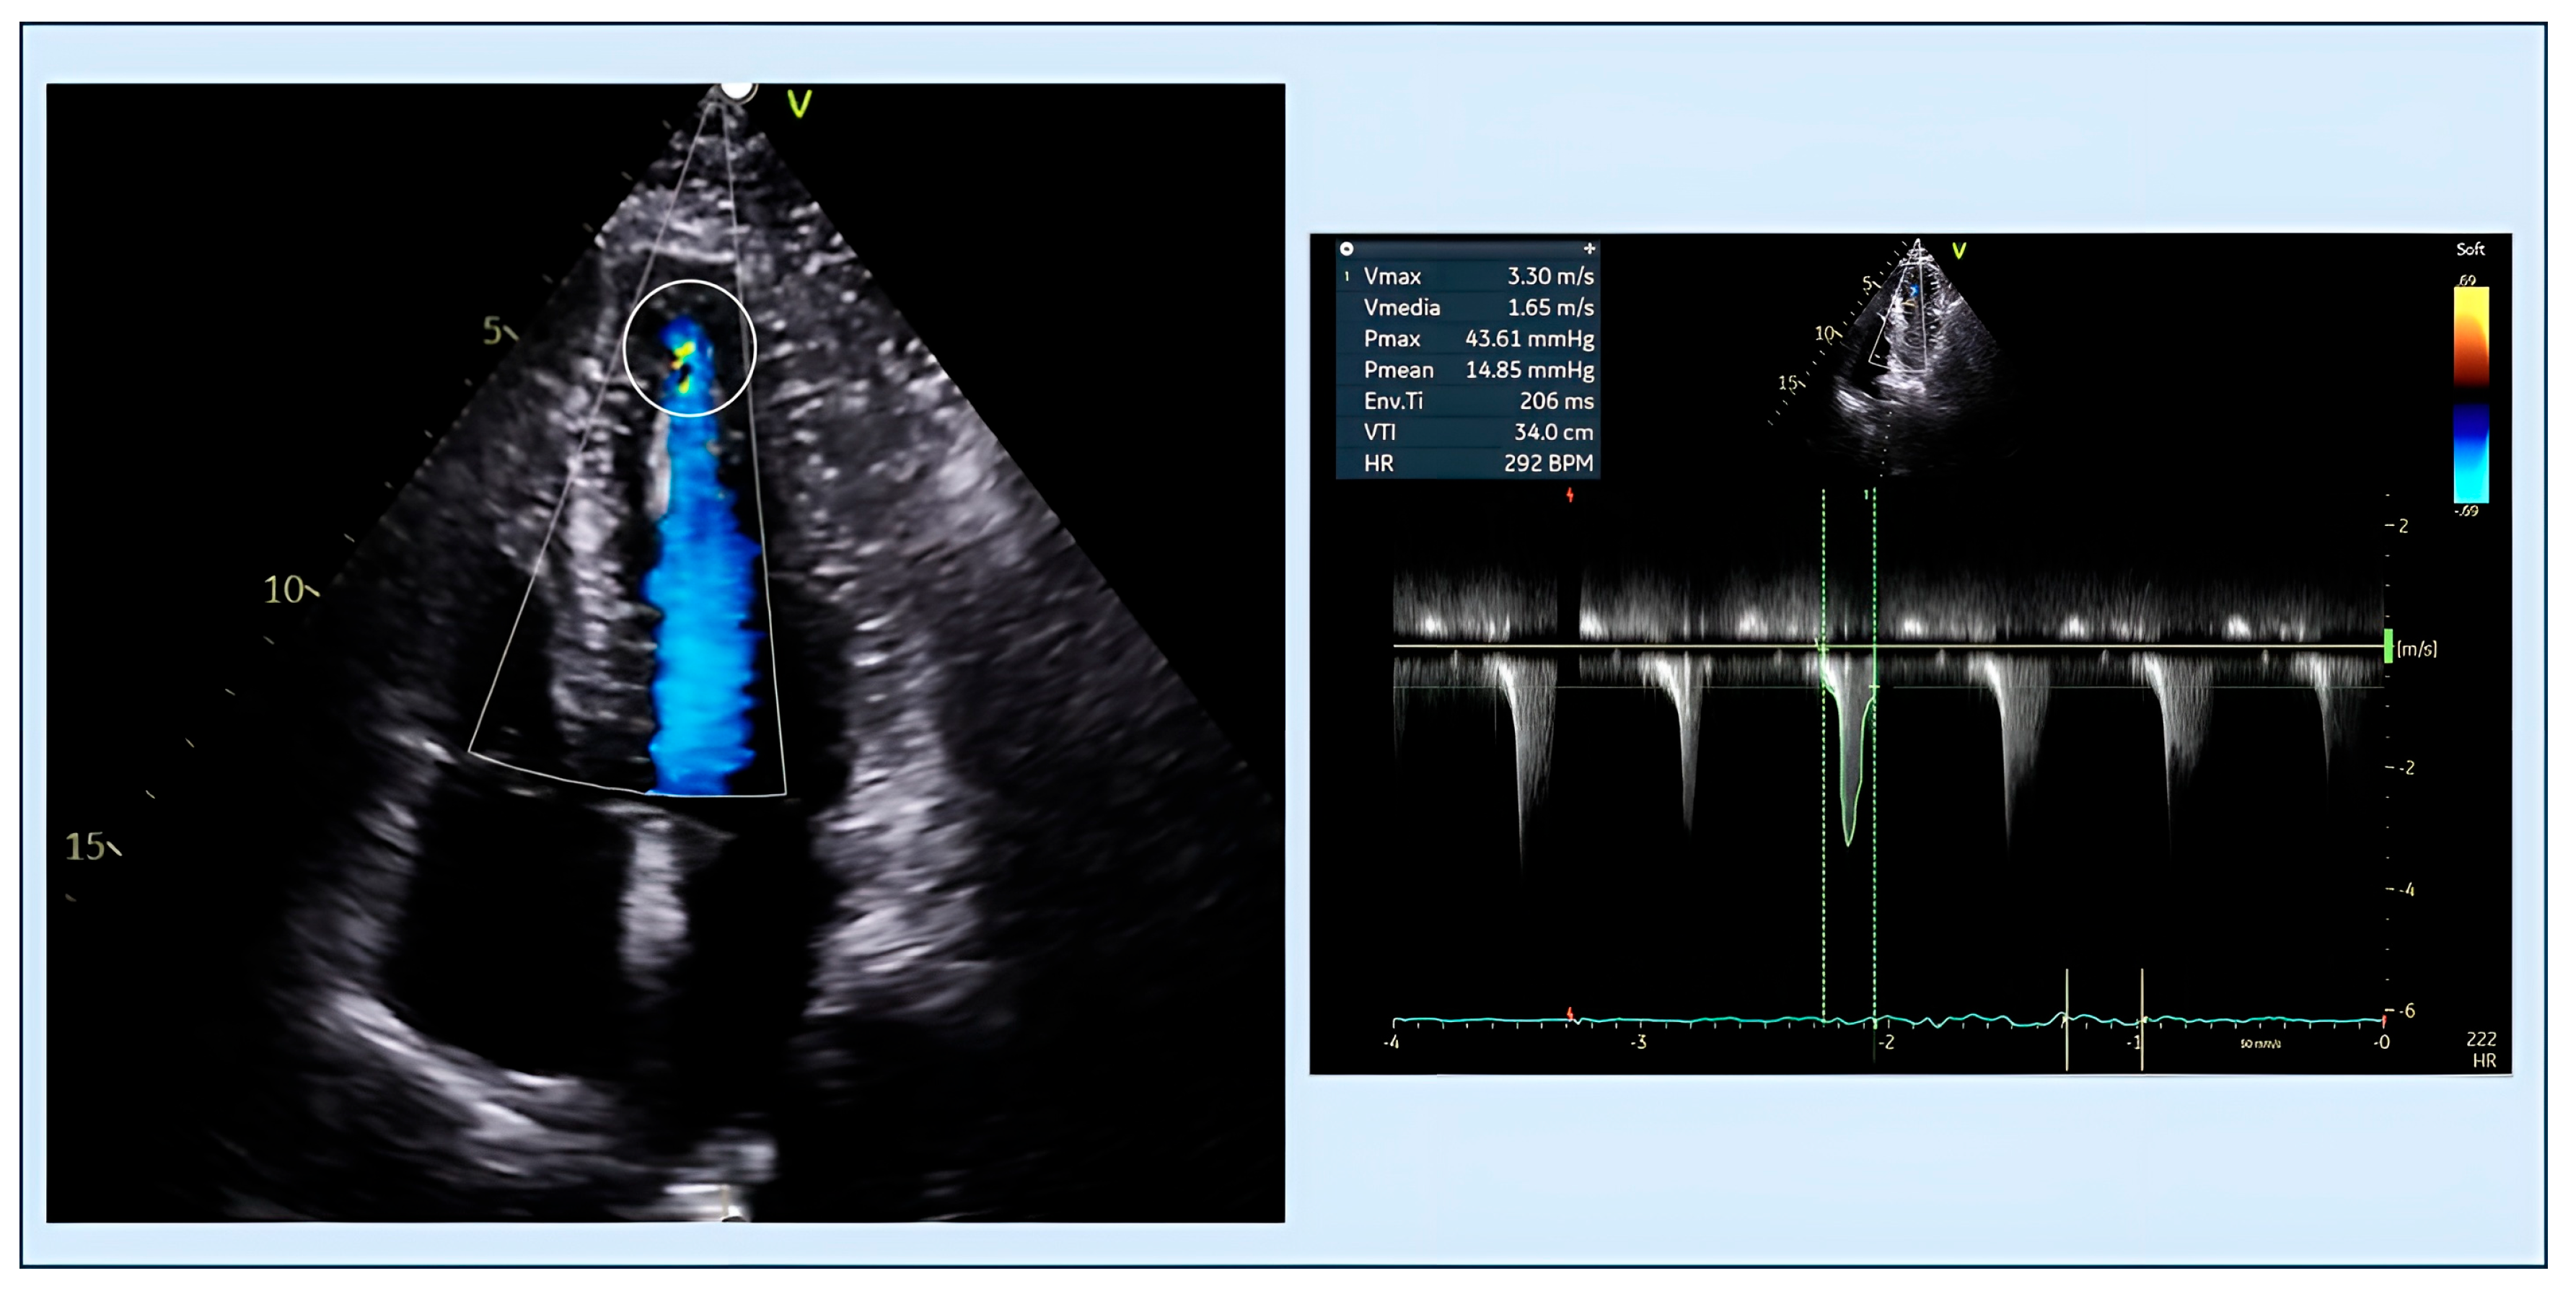

4.1. Obstruction